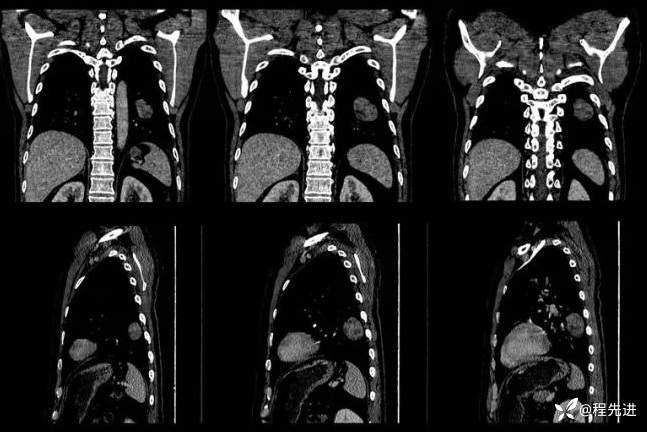

冠、矢状位重建: